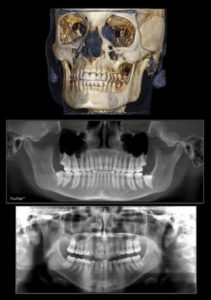

Three-dimensional radiographs provide precise data that dentists can use to make informed choices for each patient's individualized procedure and each treatment plan. The i-CAT offers many options in Cone Beam Computed Tomography (CBCT) scans to help dentists to approach innovative procedures with confidence.

For those who require a combination of 2-D and 3-D imaging, the i-CAT has you covered. The system offers both i-PAN, a traditional 2-D pan function and Tru-Pan™ that delivers precise panoramic views from 3-D scans (reconstructed pan).